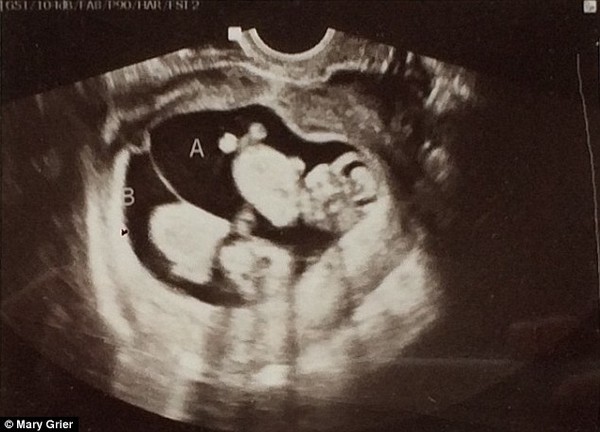

Trong lần siêu âm đầu tiên vào tuần mang thai thứ 11, cô Mary Grier - 28 tuổi, nhận được tin mình mang thai đôi. Khi biết tin, chồng cô, anh Brad - 34 tuổi không giấu nổi sự ngạc nhiên.

Trong lần siêu âm đầu tiên vào tuần mang thai thứ 11, Mary Grier, 28 tuổi, nhận được tin mình mang thai đôi. Khi biết tin, chồng cô, anh Brad, 34 tuổi không giấu nổi sự ngạc nhiên. |